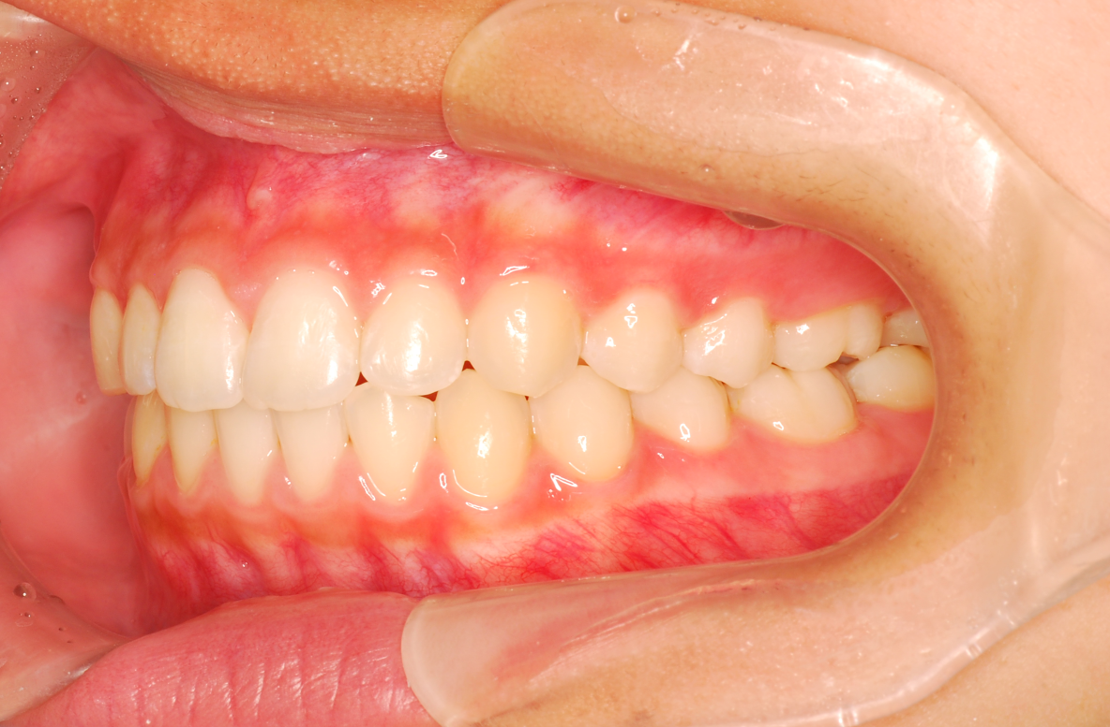

• 治療前

• 治療後

主訴:前歯の突出、抜いた奥歯のすき間を閉じてほしい

診断:上顎前突

治療内容:唇側矯正治療

年齢:17歳

治療に用いた装置:マルチブラケット装置

抜歯or非抜歯:他院にて抜歯済み

期間:30ヶ月

回数:30回

費用:1,045,000円(税込)

リスク・副作用:虫歯、歯肉炎、歯肉退縮、歯根吸収、後戻りなど